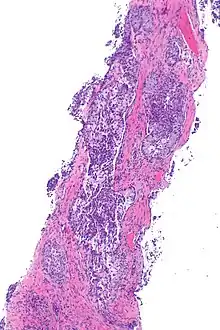

| Micrograph showing ALK positive lung adenocarcinoma. H&E stain. | |

Most lung carcinomas containing the ALK gene fusion are adenocarcinomas.

Some studies suggest that the papillary adenocarcinoma and the signet ring cell adenocarcinoma[5] variants are more likely to carry this fused gene than other histological variants.